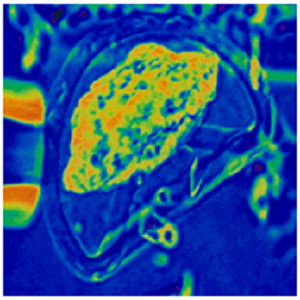

Day 6 Sheep compacted morula immediately after exposure to SYNBIOS® vitrification solution. When exposed to vitrification solution it shrunk immediately assuming the shape of a deflated ball due to rapid dehydration. This ultra-rapid vitrification technique of cryopreservation resulted in in vitro and in vivo viability comparable to fresh untreated sheep day 6 embryos. Ali and Shelton, 1992. Proceedings of the Annual Conference of the Australian Society for Reproductive Biology, Adelaide, Australia. (Ali and Shelton, J Reprod Fertil. 99:65-70, 1993).